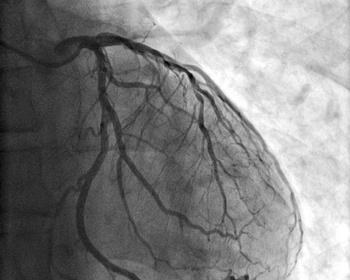

Nos travaux se basent sur l'intelligence artificielle pour analyser des images de structures vasculaires.

Nous avons proposé plusieurs approches pour la segmentation, le suivi, le recalage et la reconstruction 3D de structures vasculaires visant à assister les cliniciens dans leur pratique. Nos travaux ont mené à des percées importantes pour l'analyse d'images radiographiques. Ils permettraient également de mieux gérer l'exposition aux rayons ionisants lors des interventions cardiaques.